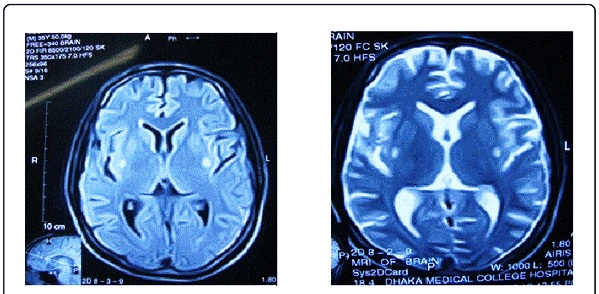

• Магнитно-резонансная томография (МРТ). Устанавливается степень поражения головного мозга, визуализируются очаги некроза и их параметры.

• Компьютерная томография (КТ). Дополнительный метод диагностики, если МРТ полностью не прояснила преобладающую клиническую картину.